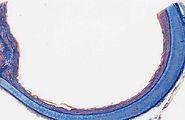

Traquea- H-E- 40X

Traquea- Tricromico Masson- 20X

Traquea- H-E- 20X

Traquea- Azan- 40X